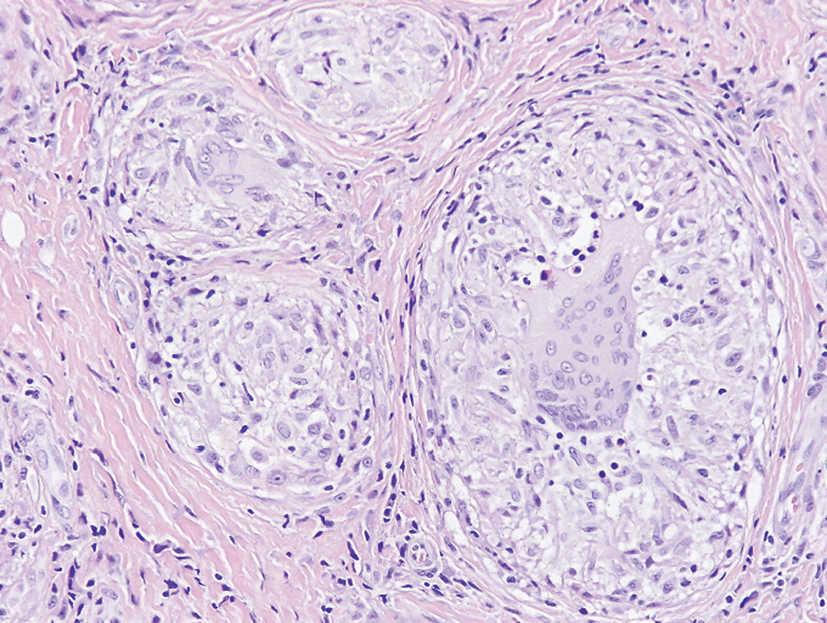

Se llevaron a cabo dos biopsias cutáneas de sendos nódulos. En el estudio histológico se pusieron de manifiesto, en el tejido celular subcutáneo, abundantes lesiones granulomatosas constituidas por linfocitos, histiocitos epitelioides y células gigantes multinucleadas, sin necrosis central o corona linfocitaria, pero rodeados de fibrosis concéntrica. En una de las biopsias estos granulomas alcanzaban la dermis profunda, respetando, en todo caso, la epidermis. Las tinciones con Zielh-Neelsen, ácido peryódico de Schiff (PAS) y metenamina argéntica resultaron negativas, así como el estudio de cristales u otros cuerpos extraños. El diagnóstico histopatológico fue dermatitis granulomatosa sarcoidea profunda (figs. 2 y 3).

Fig. 3.--Detalle de la figura 2. Se advierten estructuras granulomatosas sarcoideas redondeadas, constituidas por células epitelioides y gigantes multinucleadas, sin necrosis central ni corona linfocitaria. (Hematoxilina-eosina, x250.)